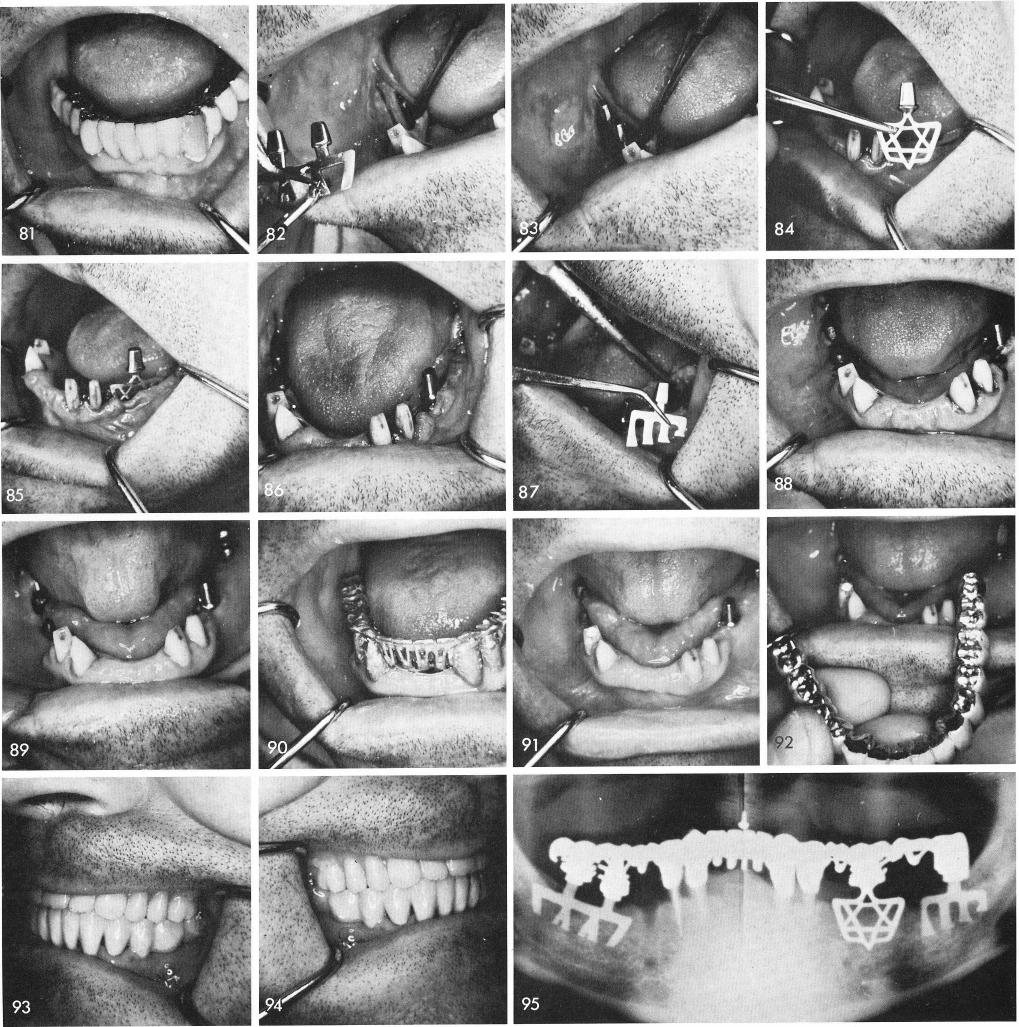

Quite often, patients, previous to implant work, neglected their teeth and practiced poor oral hygiene, fig. 81. Besides being so neglectful this man was an athiest, so I decided to put a little religion into his soul.

Grooves were made and the various designed bladevents were implanted into the bone, one of the implants, being a Vitallium "Star of David", figs. 82, 83, 84, 85, 86, 87, 88. Several weeks later after the tissues were thoroughly healed, fig. 89, the soldered castings were fitted, fig. 90. By the fourth week the tissues looked well clinically and the blades were firm inside the bone, fig. 91, and the finished prosthesis was cemented, figs. 92, 93, 94. A final x-ray was taken, fig. 95.

1 Vitallium Star of David mandibular implant design